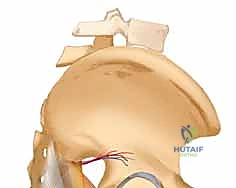

إن الحوض البشري هو جسر ميكانيكي حيوي يربط المحور المركزي للجسم (العمود الفقري) بالأطراف السفلية، ويوفر درعاً حامياً للأعضاء الداخلية الحيوية مثل المثانة، الأمعاء، والأوعية الدموية الكبرى. عندما يتحطم هذا الدرع نتيجة قوة هائلة، فإن الخطر لا يقتصر على العظام فحسب، بل يمتد ليشمل نزيفاً داخلياً قد يكون مميتاً إذا لم يتم احتواؤه فوراً باستخدام تقنية التثبيت الخارجي.

الأوعية الدموية والأعصاب: حقل ألغام جراحي

ما يجعل جراحة الحوض، وتحديداً كسور الحوض، في غاية الخطورة هو شبكة الأوعية الدموية الكثيفة التي تبطن الجدران الداخلية للحوض. الشرايين والأوردة الحرقفية (Iliac vessels) تمر مباشرة عبر هذه المنطقة. عند حدوث كسر، يمكن للحواف العظمية الحادة أن تمزق هذه الأوعية، مما يؤدي إلى نزيف حوضي هائل. هنا يتدخل الأستاذ الدكتور محمد هطيف بخبرته الطويلة في التعامل مع هذه الحالات الحرجة، حيث يدرك تماماً كيف يتجنب إلحاق المزيد من الضرر بهذه الهياكل الحيوية أثناء تثبيت الكسر.